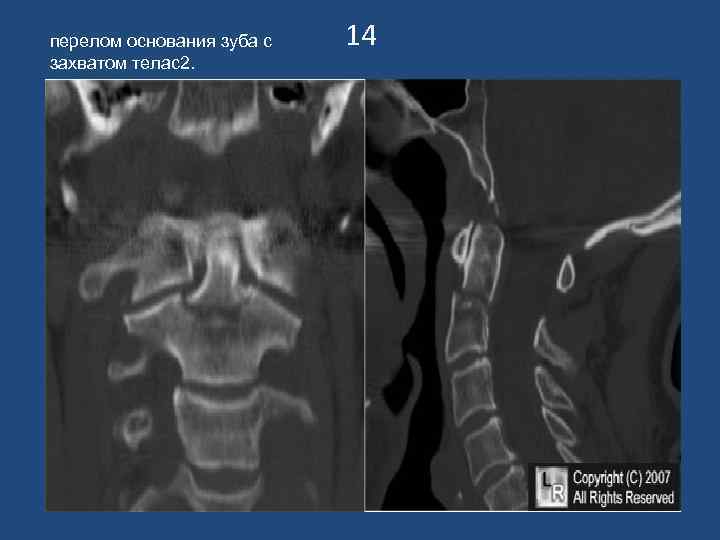

перелом основания зуба с захватом телас2. 14